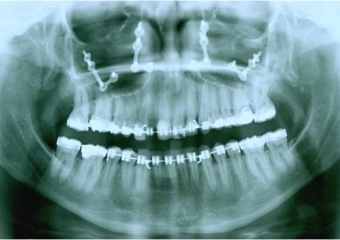

Raio X inicial - Clínica Cliniface

Raio X inicial